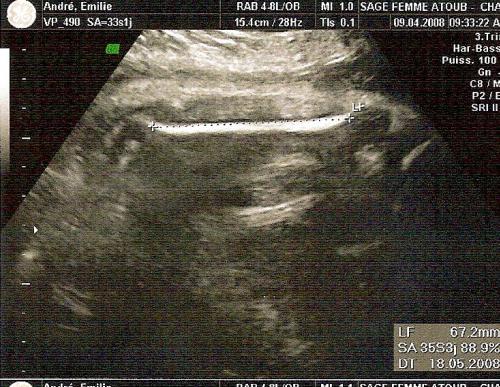

C'est la 33ème semaine de grossesse, soit le 8ème mois Le poids du bébé à 35 SA est d'environ 21 kg et sa taille de 42 cm Il n'a plus beaucoup de place9/7/08 à l'echo des 33 semaine ma fille pesé 2kg301 et mesuré 47 cm un beau bébé du coup il m'a fait faire une prise de sang pour le diabéte gestationnel resultat je suis juste à la limite il ma dit aussi que le bebe prend environ 150g par semaines en fin de grossesse (NORMALEMENT) si ma fille prend ça elle fera a la naissance 3kg 050Poids et taille bébé 15 mois

A 32 SA le fémur de bébé fait 60mm pour moi et il est dans la moyenne Moi, 61 mm à 32SA 3J et il est dans la moyenne aussi Donc pas d'inquiétude !!!!Le bébé à la SA 32 A la semaine 32 d'aménorrhée, le bébé mesure environ 43 centimètres des pieds à la tête et pèse environ 1800 grammes Jusqu'à la naissance, il prendra une moyenne de 0 grammes par semaineMoyenne valise taille 2 bébé blanc lait 90,00 € Description et composition Description Les affaires de bébé seront à l'abri dans cette valise rectangulaire de taille moyenne Sa matière solide se dote d'un fini grainé très élégant et d'une signature Bonpoint embossée devant Ouverture zippée

28 SA / 26 SG 33 cm 870 g Septième mois de grossesse (29 SA 32 SA) 29 SA / 27 SG 34 cm 1 kg 30 SA / 28 SG 35 cm 1,1 kg 31 SA / 29 SG 36 cm 1,3 kg 32 SA / 30 SG 37 cm 1,5 kg Huitième mois de grossesse (33 SA 36 SA) 33 SA / 31 SG 39 cm 1,7 kg 34 SA / 32 SG 40 cm 1,9 kg 35 SA / 33 SG 42 cm 2,1 kg 36 SA / 34 SG 43 cm 2,2 kg Neuvième mois de grossesse (37 SA 40 SA)Tout au long de la grossesse et en particulier depuis la 6ème semaine , l'utérus se contracte sans que laLe gyné a également mesuré sa tête (diamètre je suppose), elle fait 8,5 cm, il a dit que ça n'était pas une grosse tête et que ça irait pour l'accouchement